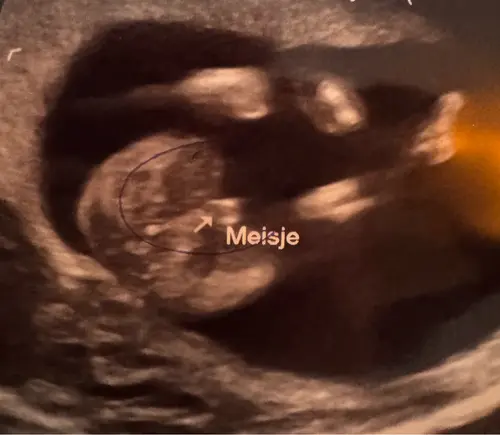

Toevoeging: ik vroeg dus nog of het normaal is dan dat het uitsteekt, ondanks dat het een meisje is & ze zei dus “ja dit is echt een meisje, het is eerst gewoon nog wat meer opgezet

Betreft het uitsteeksel heeft ze gelijk. Ook bij meisjes steeks het wat uit, alleen is er dan een driedeling te zien (bij jou ook), dus wit, donkerder, wit. Een “hamburgertje”😍 gefeliciteerd!!

Jaa, wij hadden ook zo’n soort foto met de 13 weken echo😂 dus ik daardoor overtuigd van een jongen. Maar bleek toch een meisje afgelopen maandag